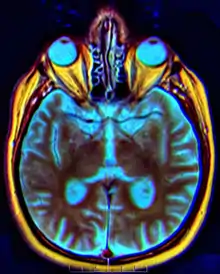

Quiasma óptico

O quiasma óptico é uma estrutura em formato de X formada pelo encontro de dois nervos ópticos. Localiza-se na parte anterior do assoalho do III ventrículo. Recebe as fibras dos nervos ópticos, que ai cruzam em parte e continuam nesse trato que se dirigem aos corpos geniculados laterais. Como resultado temos que cada hemisfério cerebral recebe informações sobre o campo visual contralateral de ambos os olhos. Ver olho.

O quiasma óptico (em vermelho).